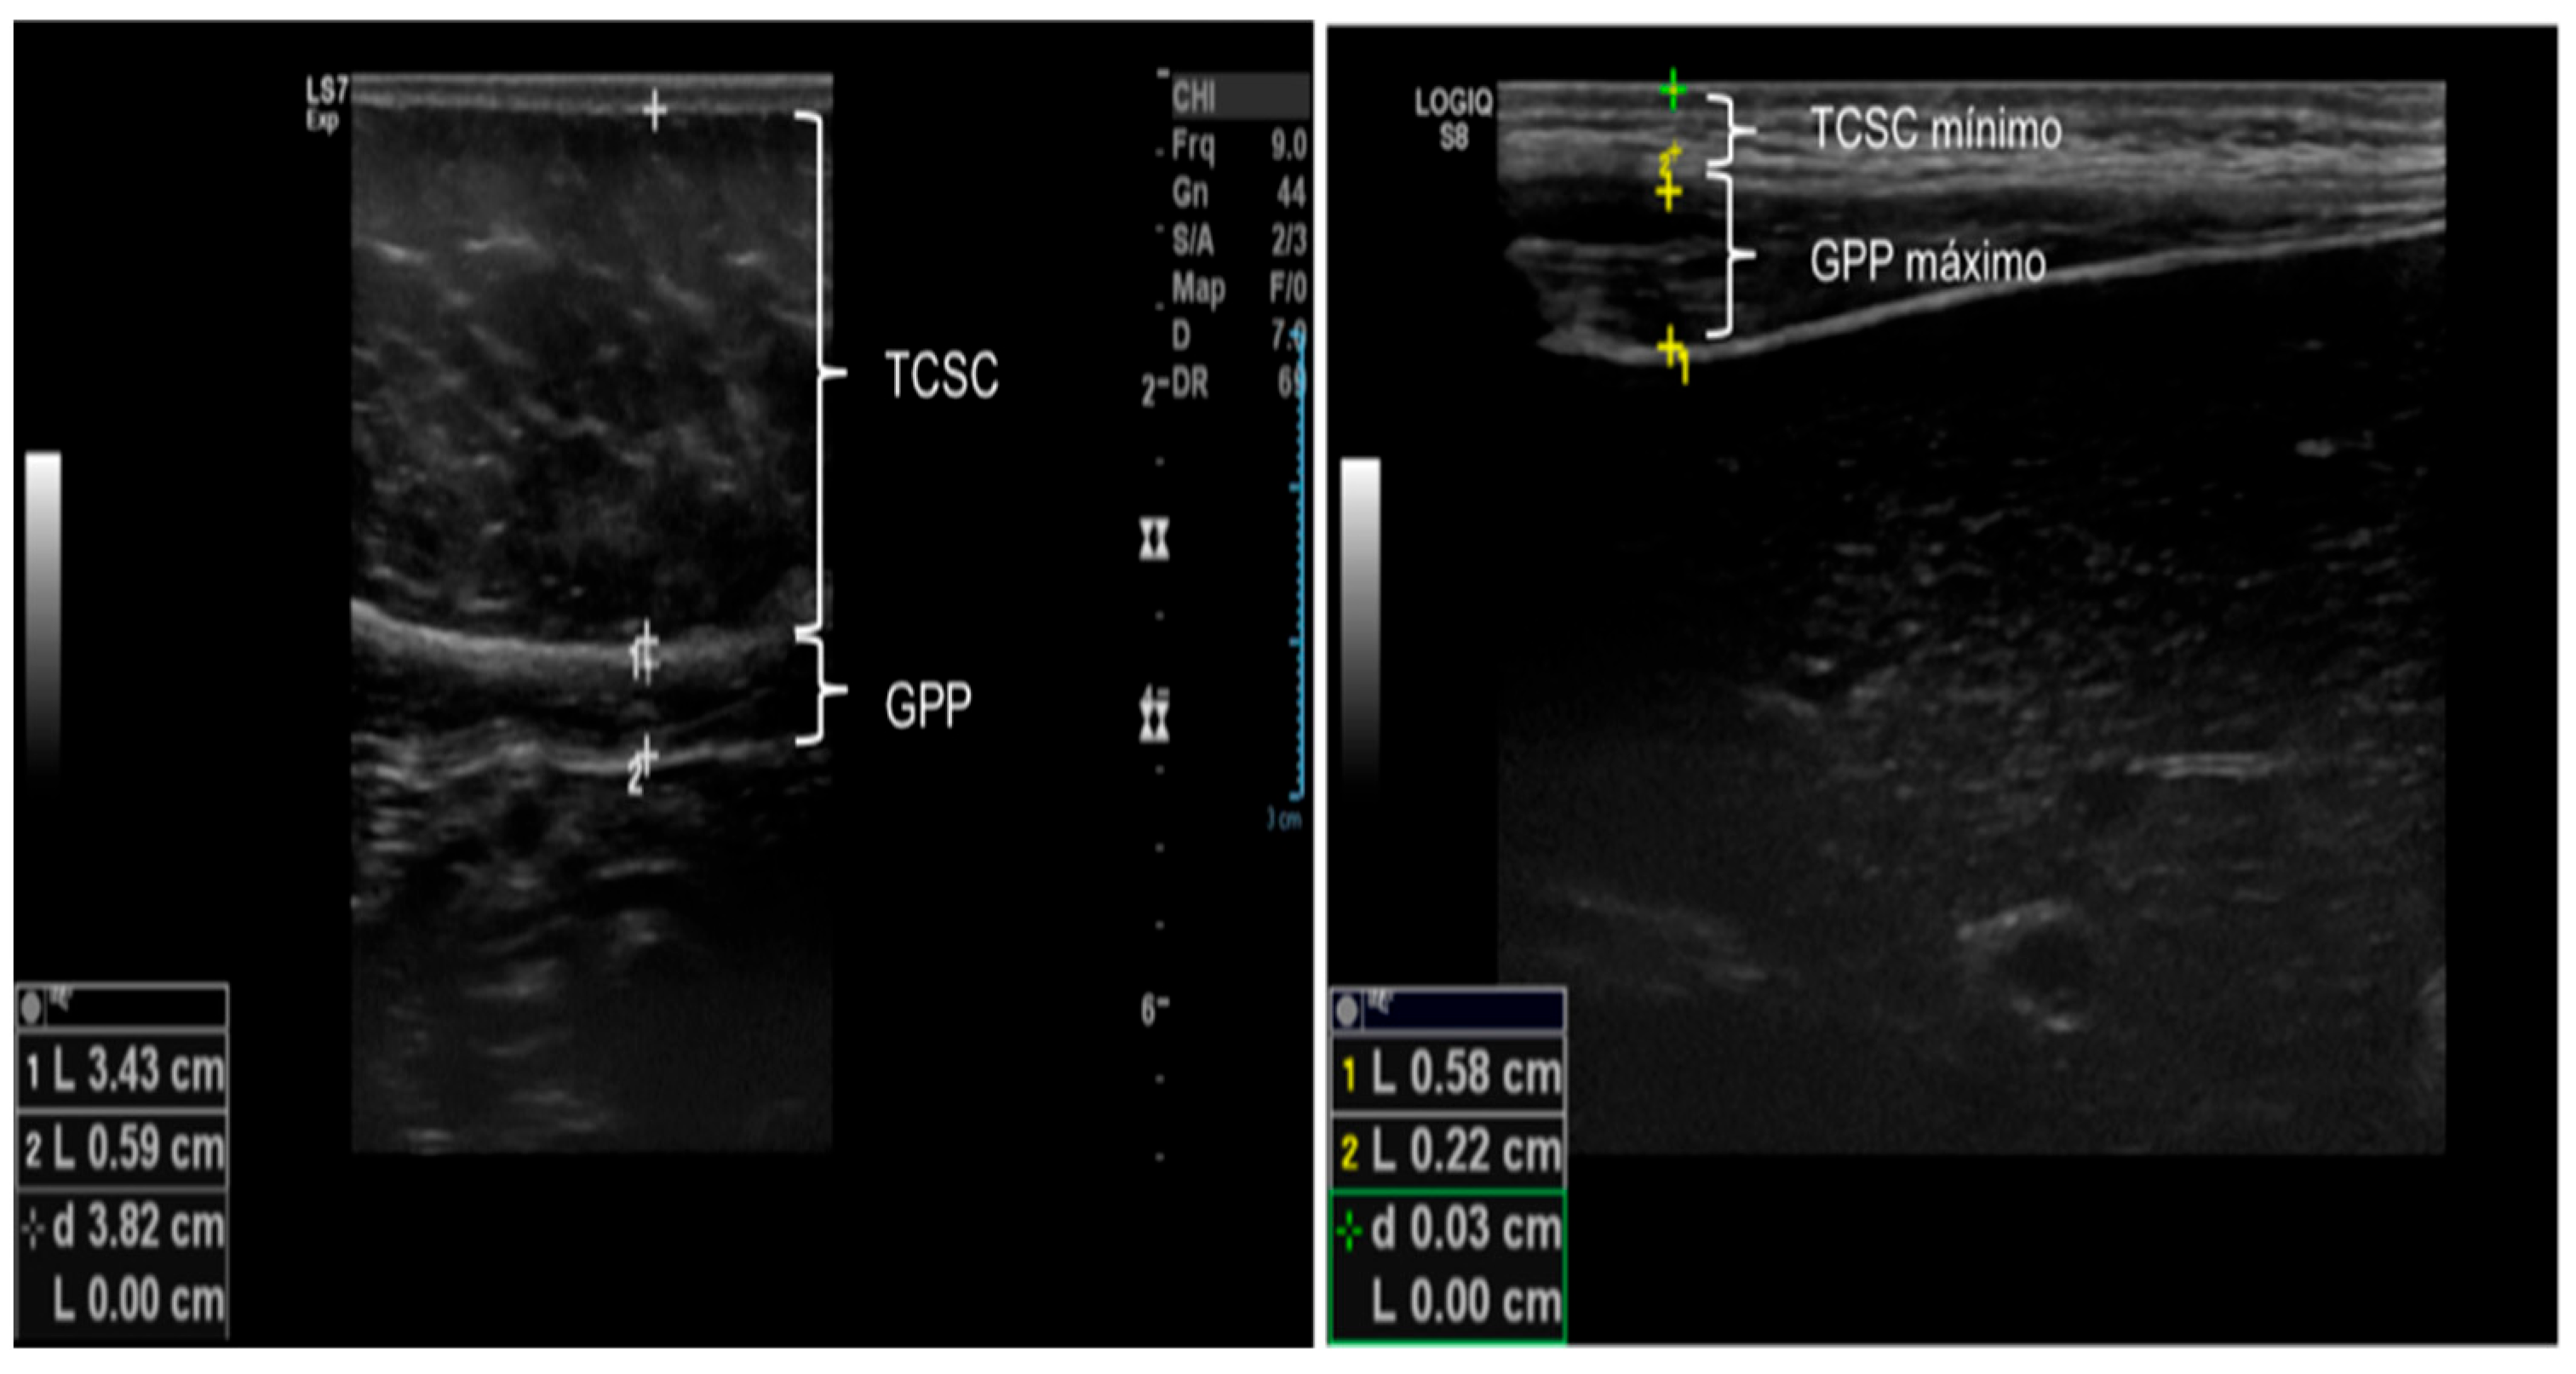

2.2.2. Ultrasound of Subcutaneous and Intra-Abdominal Fat

| Subcutaneous cellular tissue (SCCT, cm) | 0.43 ± 0.28 | 1.03 ± 0.71 | 1.66 ± 0.75 | 0.001 * |

| Minimum subcutaneous cellular tissue (minimum SCCT, cm) SCCT | 0.34 ± 0.16 | 0.65 ± 0.48 | 1.08 ± 0.51 | <0.001 *& |

| Maximum subcutaneous cellular tissue (maximum SCCT, cm) | 0.56 ± 0.34 | 1.19 ± 0.77 | 1.83 ± 0.78 | 0.010 * |

| Preperitoneal fat (PPF, cm) | 0.12 ± 0.04 | 0.14 ± 0.09 | 0.15 ± 0.09 | 0.583 |

| Minimum preperitoneal fat (minimum PPF, cm) | 0.12 ± 0.03 | 0.12 ± 0.07 | 0.12 ± 0.05 | 0.101 |

| Maximum preperitoneal fat (maximum PPF, cm) | 0.58 ± 0.27 | 0.76 ± 0.25 | 0.91 ± 0.26 | <0.001 * |